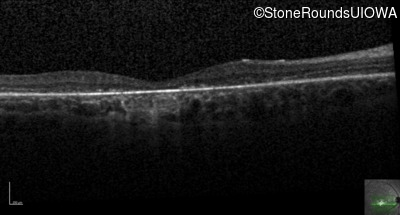

Age at visit: 26 years

Age at visit: 27 years

Age at visit: 31 years